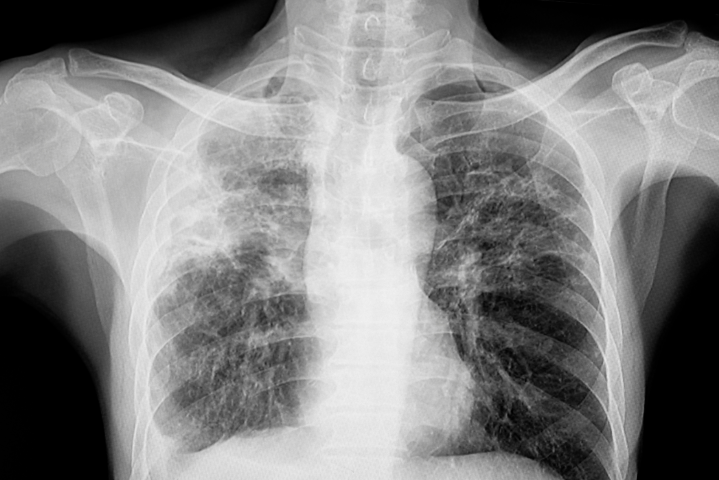

胸部X光显示肺结核(TB)以上肺叶为主的病变,可累及左肺、右肺或双肺。